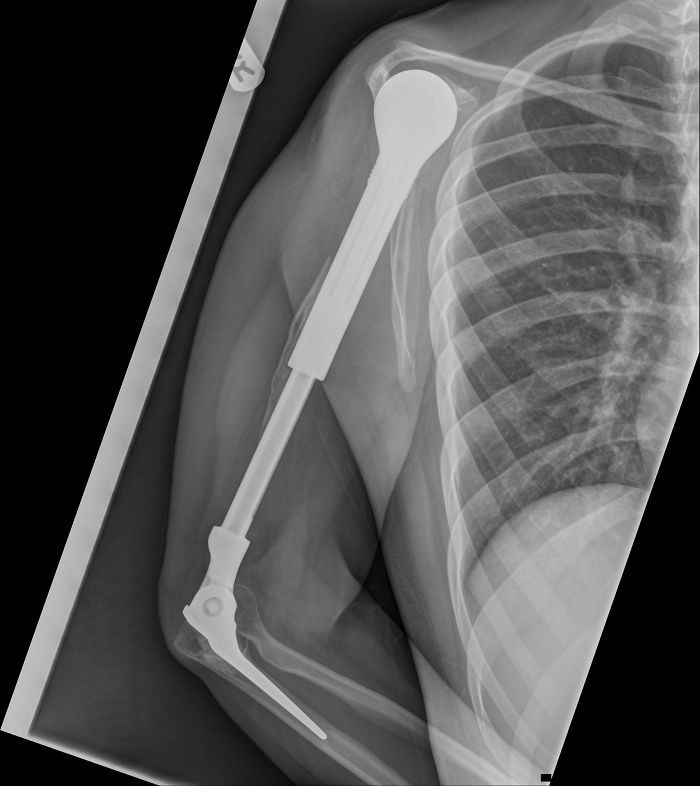

文章插图

我的金属手臂的X射线